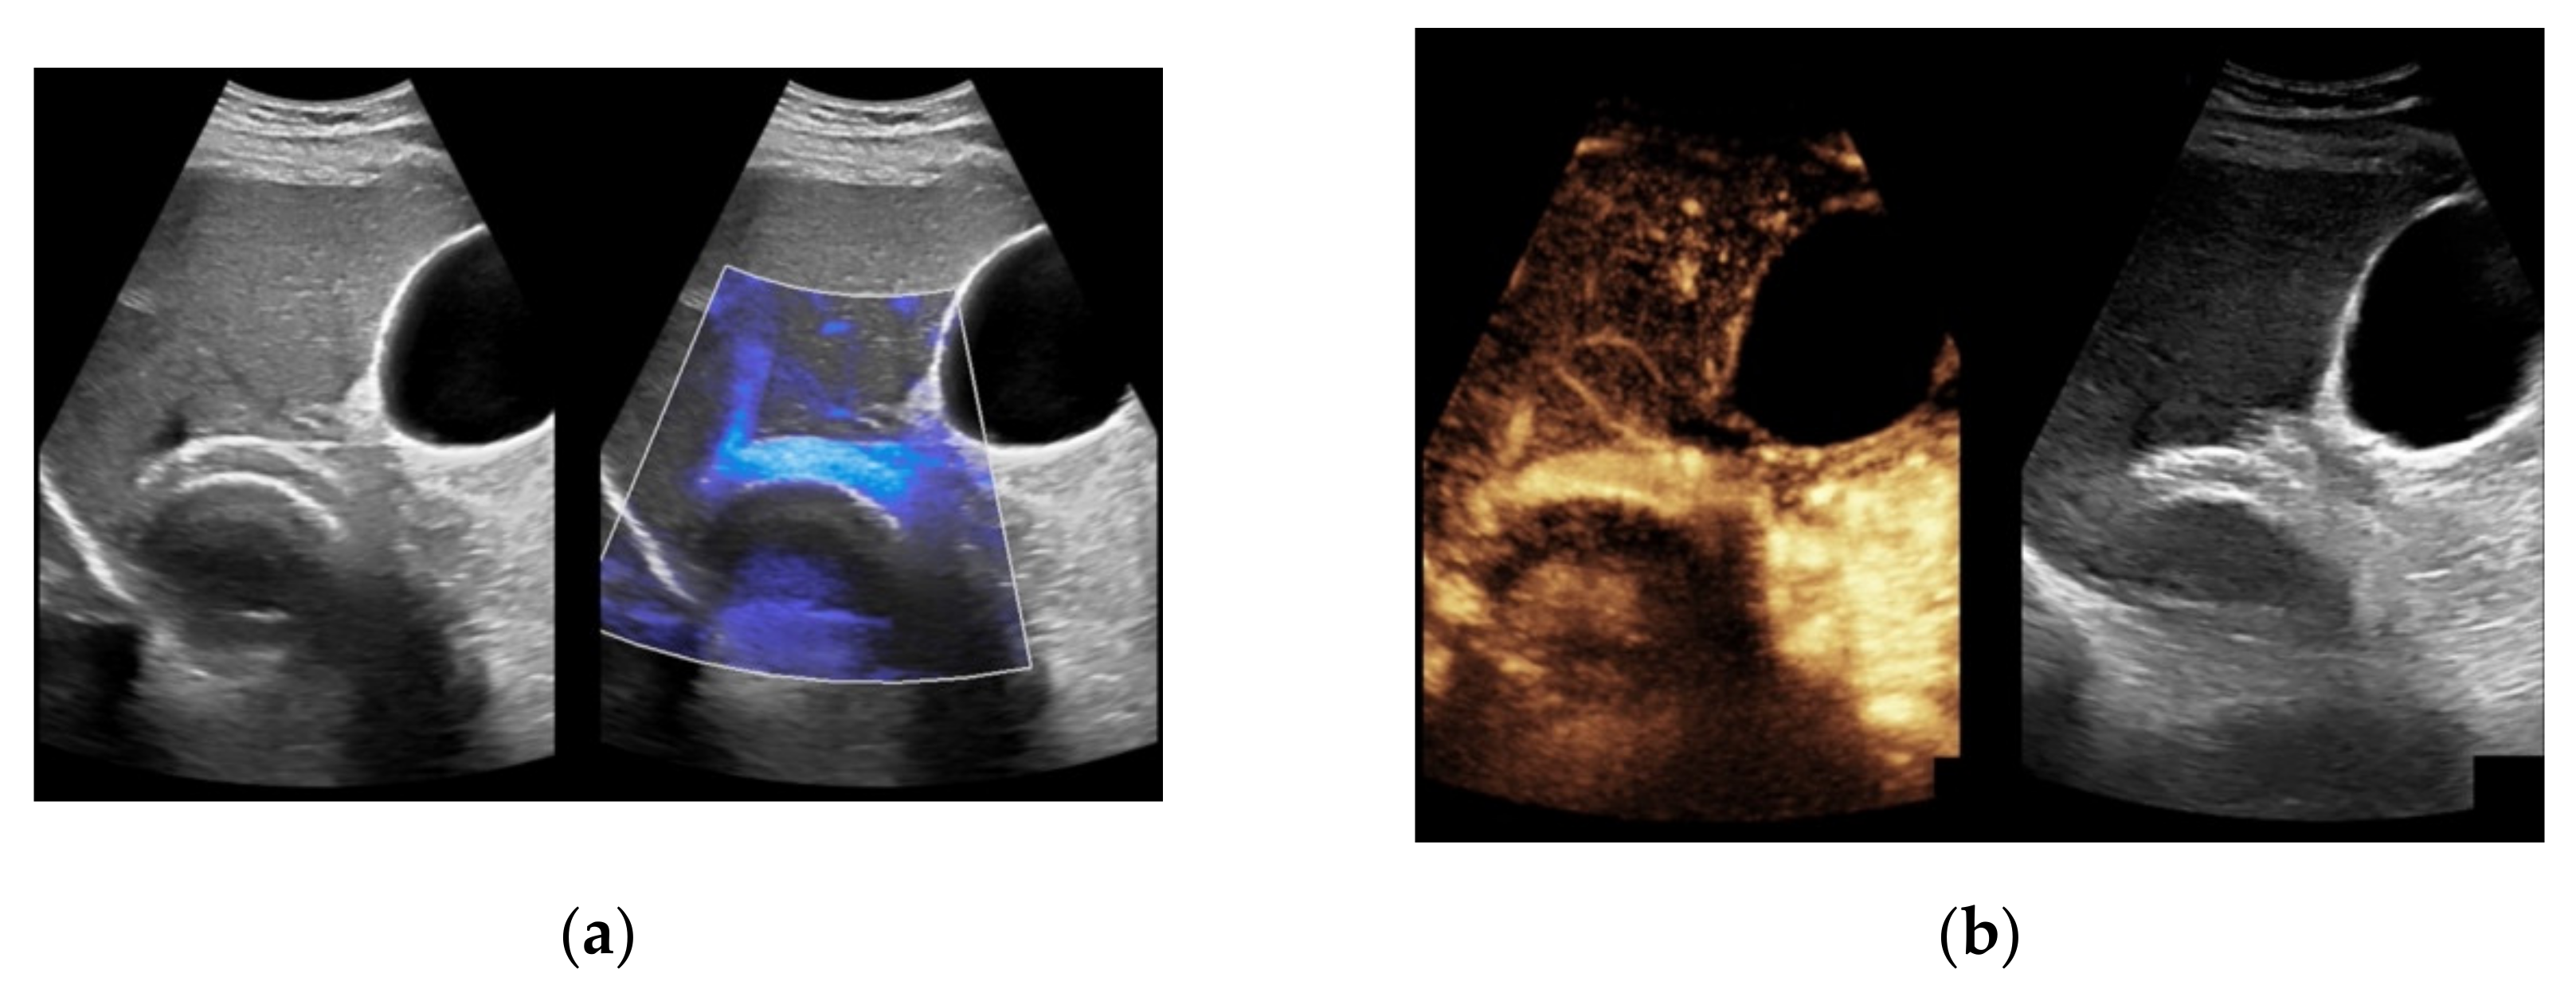

Figure 7. 52-year-old female patient with irregular presentation of the transjugular intrahepatic portosystemic shunt (TIPS) on B-mode ultrasound (a) and partial flow on Color Doppler ultrasound (CDUS) (b). After contrast administration, in contrast to CDUS, regular and continuous contrast of the TIPS is seen without evidence of thrombotic alterations or occlusion (c).

Considering findings from CDUS and CEUS examination, in eight patients results were inconsistent (7.6%). Five patients who were only partially assessed via Color Doppler ultrasound showed a regular perfusion by using CEUS (Figure 7), two patients in whom inconspicuous TIPS perfusion was registered by CDUS showed partial occluding stent thrombosis by CEUS while in one patient suspected stent thrombosis in CDUS could not be verified by CEUS (Table 3).